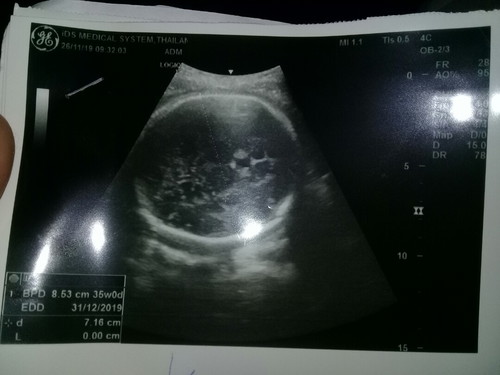

ในใบซาวน์นี้ไม่มียอกน้ำหนักค่ะแม่ มีแต่อายุครรภ์และขนาด